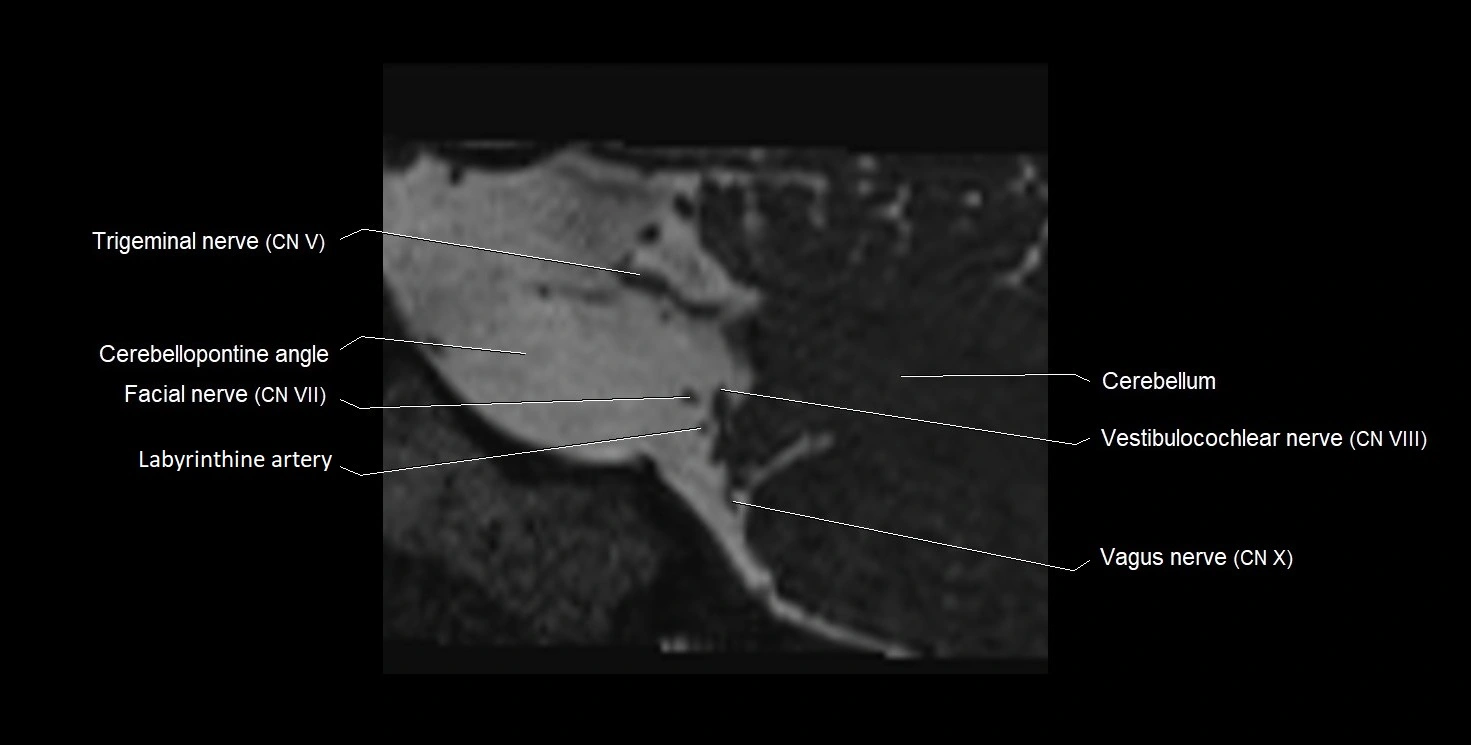

MRI images

image